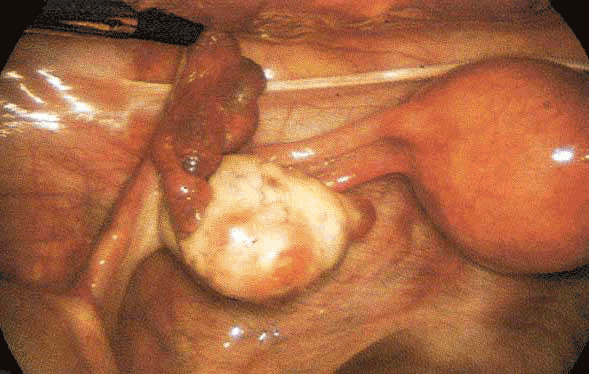

Aspect cœlioscopique de l'utérus et ses annexes gauches (trompe de Fallope, ovaire, ligament utéro-ovarien, ligament lombo-ovarien, la feuille postérieure du ligament large et le ligament utéro-sacré gauche).